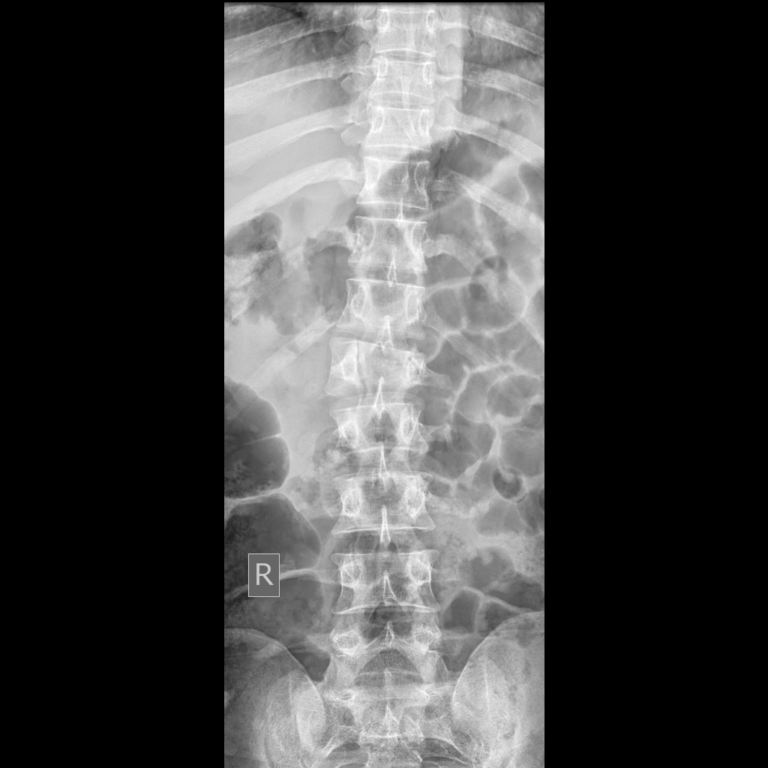

Diseases and injuries of the backbone are among the most common afflictions of humankind and one of the major reasons for seeking orthopaedic consultation. The backbone is made up of individual bones called vertebrae, which are bound together by a specialized tissue known as the intervertebral disc, commonly referred to as the disc.

The most common cause of back and neck pain is slipping of the disc, which leads to compression of the nerves or the spinal cord. Nerve compression causes pain that originates in the neck or back and radiates down the arm or leg — a condition commonly known as sciatica. Compression of the spinal cord can result in weakness or even paralysis of the arms or legs. A slipped disc is therefore a serious condition that requires immediate medical attention.

Another cause of back pain is lumbar canal stenosis, a condition in which the space through which the spinal cord passes becomes narrow and starts pressing on the spinal cord. This results in back pain and weakness of the limbs. Fractures of the backbone with bone fragments pressing on the nerves are considered a surgical emergency. In some patients, the backbone may shift out of its normal position, causing severe back pain — a condition known as spondylolisthesis.

All these conditions require surgery to prevent the worsening of symptoms and to avoid neurological complications. In the past, spine surgery was extensive and laborious. Extensive dissection of the muscles, removal of major portions of the back bone, prolonged bed rest, and restriction of activities were all common complications associated with traditional spine surgery.